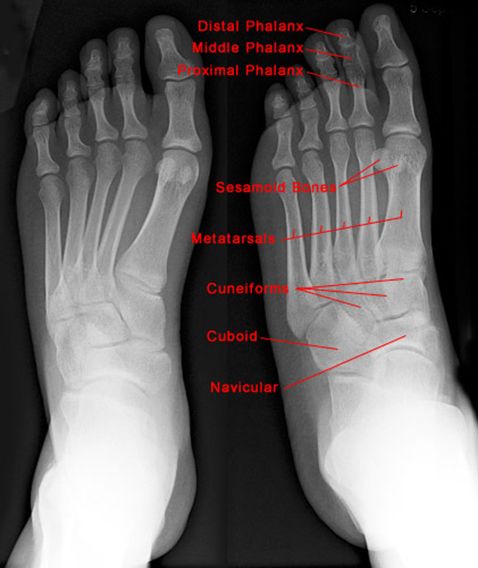

正常足正位片

疼痛科怎么理疗疼痛科医生、康复理疗科医生、针刀针灸医生应掌握的常见骨科疾病X光片_https://www.jmylbn.com_新闻资讯_第43张